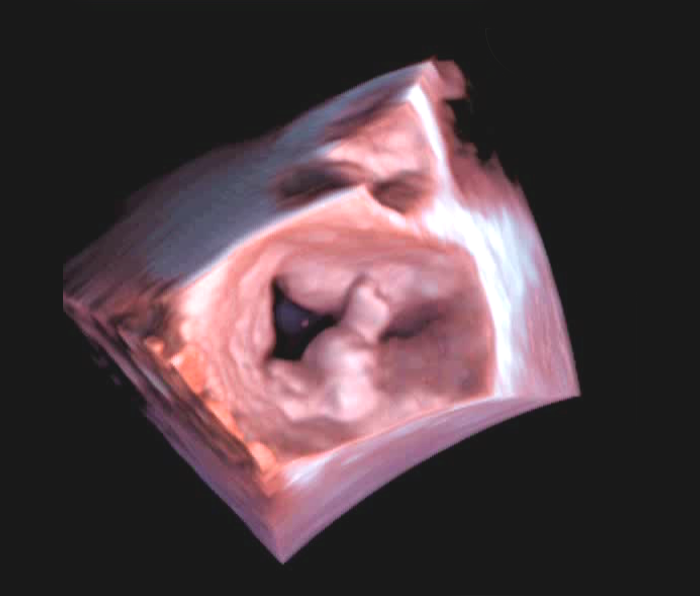

Uprzejmie informujemy, iż na stronie internetowej Asocjacji w sekcji WADY SERCA W OBRAZACH umieśliśmy nowy przypadek: Pierwotna niedomykalność mitralna w mechanizmie wpadania płatka tylnego.